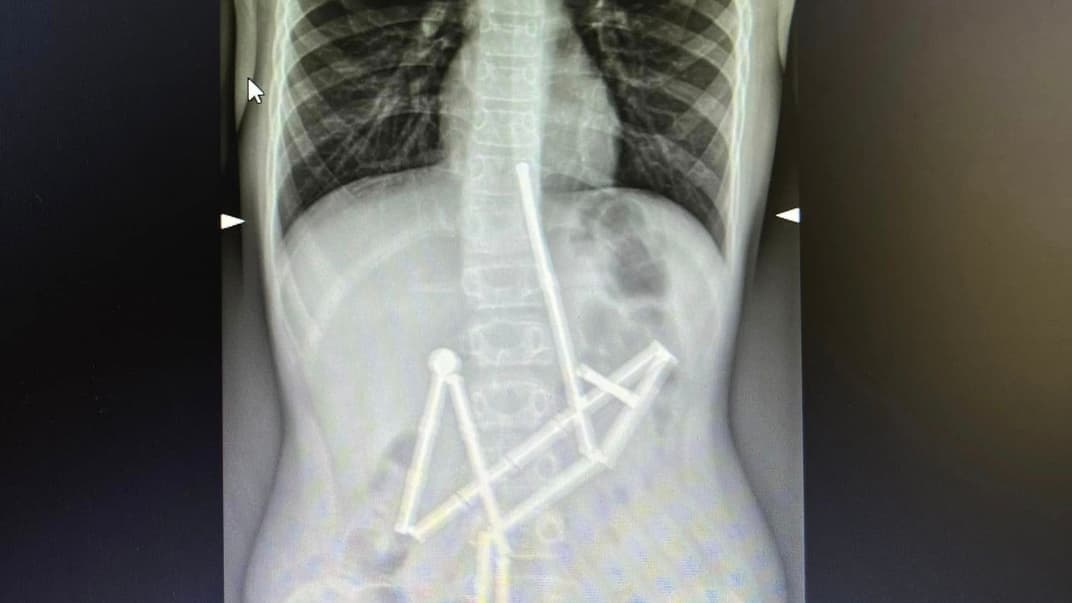

До лікарів звернулися батьки дитини, що скаржилась на біль у животі. Вже на першому рентген-знімку медики побачили, що у його травному каналі є ціла група сторонніх тіл. У них вдалося впізнати магнітний конструктор. 20 магнітів були в різних частинах шлунково-кишкового тракту, проте були зʼєднані між собою.

Під час операції у дитини виявили 5 перфоративних отворів у черевній порожнині та останній елемент конструктора. Всі отвори закрили, а магніт видалили.